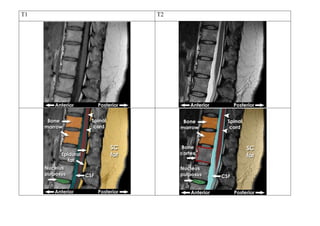

T1-weighted image – Anatomy (spine)

T1 images can be thought of as a map of proton energy within

fatty tissues of the body

Fatty tissues include subcutaneous fat (SC fat) and bone marrow

of the vertebral bodies

Cerebrospinal fluid (CSF) contains no fat – so it appears black on

T1-weighted images

T2-weighted image – Anatomy (spine)

T2 images are a map of proton energy within fatty AND water-

based tissues of the body

Fatty tissue is distinguished from water-based tissue by

comparing with the T1 images – anything that is bright on the

T2 images but dark on the T1 images is fluid-based tissue

For example, the CSF is white on this T2 image and dark on the

T1 image above because it is free fluid and contains no fat

Note that the bone cortex is black – it gives off no signal on either T1 or T2 images because it contains no free

protons